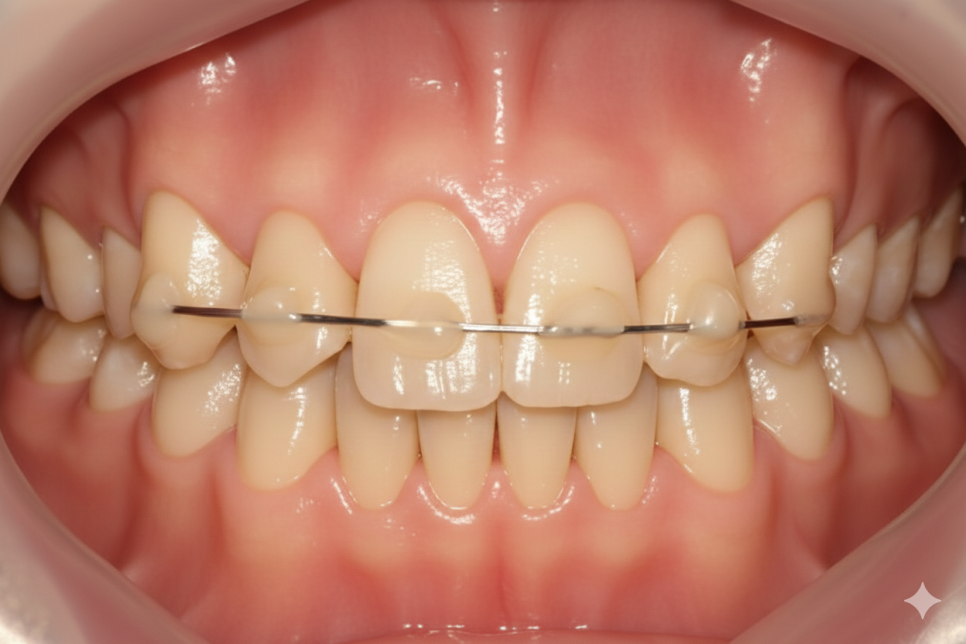

잠간고정술은 이름 그대로

임시로 치아를 고정한다는 뜻이에요.

잇몸 질환이나 외상으로 흔들리는 치아가

안정을 찾고 회복될 수 있도록,

인접한 튼튼한 치아들에

철사나 레진으로 묶어두는 시술이죠.

치아가 흔들리면 주변 조직이

아물 기회를 얻지 못하기 때문에

인위적으로 움직임을 제한해

치유를 돕는 일종의

'치아 깁스'라고 이해하시면 쉬워요.

또 임플란트로 진행하는 경우에

반대편 치아가 내려오지 못하게

임플란트 완성 전까지

철사로 묶어놓는 방식을 쓰기도 합니다.